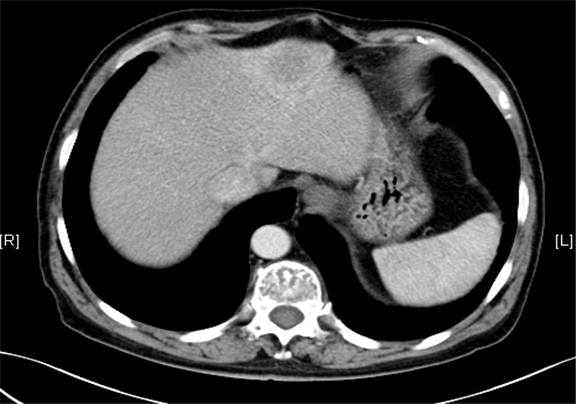

术前CT检查:

平衡期

下腹部增强CT示:肝左外叶占位,考虑恶性肿瘤伴门脉侵犯可能性大,符合肝硬化表现。

现病史:患者5月前因“肝硬化”行上腹部CT发现肝占位性病变(未见报告),建议随访观察,患者无乏力、恶心、呕吐、腹胀、腹泻、血便、食欲减退,无寒战,无头痛头晕,无皮肤粘膜黄染,无尿频、尿急、尿痛、血尿。3天前再行上腹部增强CT检查示:肝左外叶占位,考虑恶性肿瘤伴门脉侵犯可能性大,建议MR平扫+强化符合肝硬化表现。双肾多发小囊肿可能性大